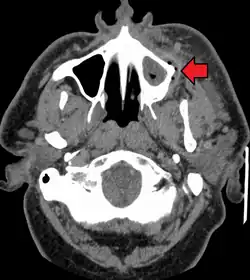

In some cases, a tooth abscess may perforate bone and start draining into the surrounding tissues creating local facial swelling. In some cases, the lymph nodes in the neck will become swollen and tender in response to the infection. It may even feel like a migraine as the pain can transfer from the infected area. The pain does not normally transfer across the face, only upward or downward as the nerves that serve each side of the face are separate.

If left untreated, a severe tooth abscess may become large enough to perforate bone and extend into the soft tissue eventually becoming osteomyelitis and cellulitis respectively. From there it follows the path of least resistance and may spread either internally or externally. The path of the infection is influenced by such things as the location of the infected tooth and the thickness of the bone, muscle and fascia attachments.

Internal drainage is of more concern as growing infection makes space within the tissues surrounding the infection. Severe complications requiring immediate hospitalization include Ludwig's angina, which is a combination of growing infection and cellulitis which closes the airway space causing suffocation in extreme cases. Also infection can spread down the tissue spaces to the mediastinum, causing significant consequences on the vital organs such as the heart. Another complication, usually from upper teeth, is a risk of sepsis traveling through pathways to which it can possibly lead to endocarditis, brain abscess (extremely rare), or meningitis (also rare).